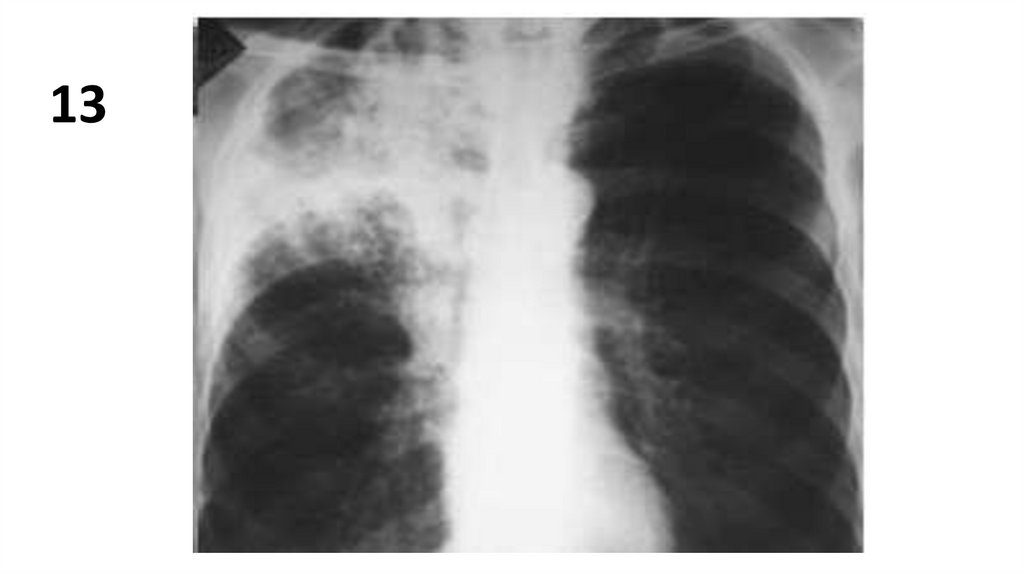

13.

14.

13